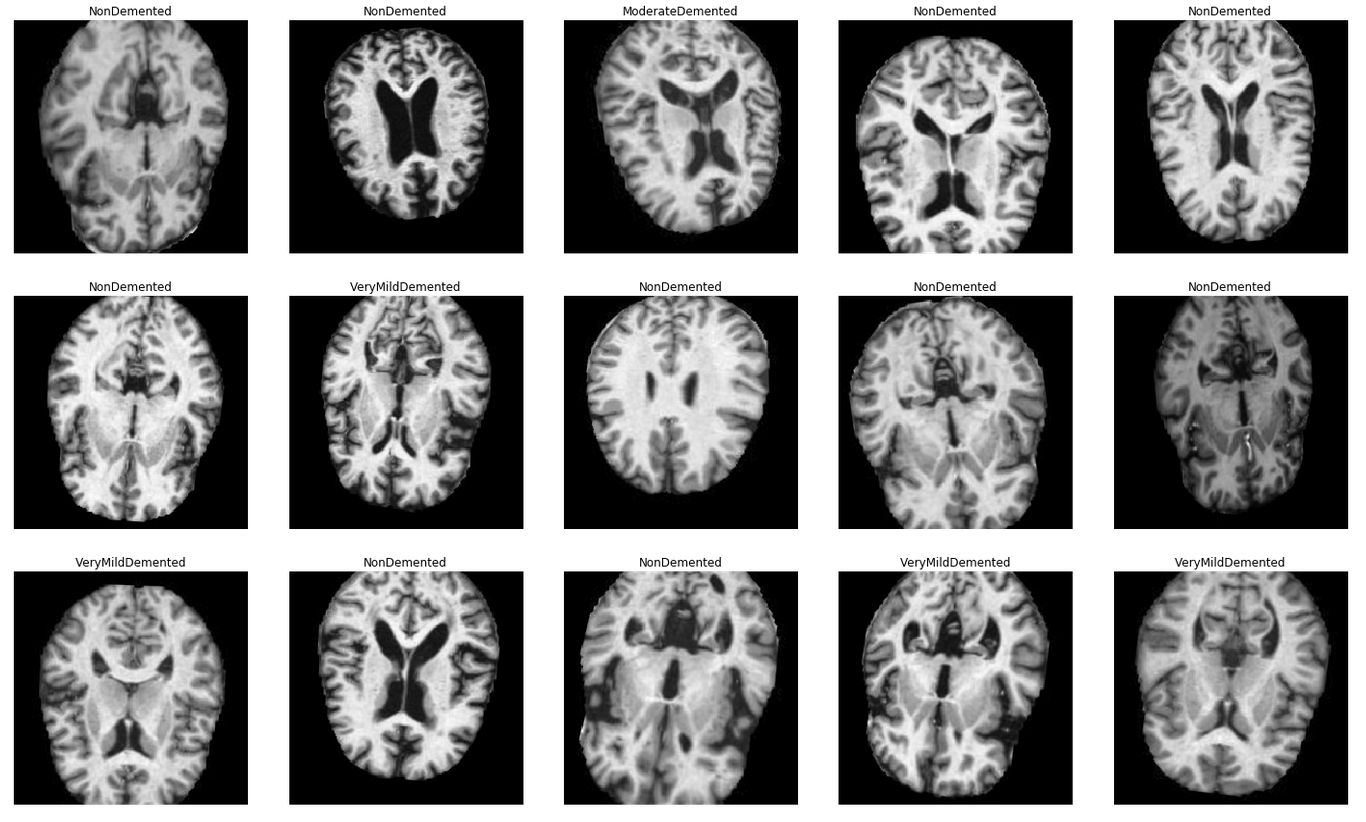

Clasificación de distintos tipos de Alzheimer.

El data set que vamos a utilizar para esta demostración proviene de esta competencia de kaggle. Las imágenes consisten en un conjunto de resonancias magnéticas clasificadas por la gravedad de los síntomas de Alzheimer que presentan los pacientes: Ninguno, Suave, Muy Suave o Moderado.

Vamos a utilizar este conjunto de imágenes para armar un modelo de clasificación que posteriormente podamos implementar como un microservicio.